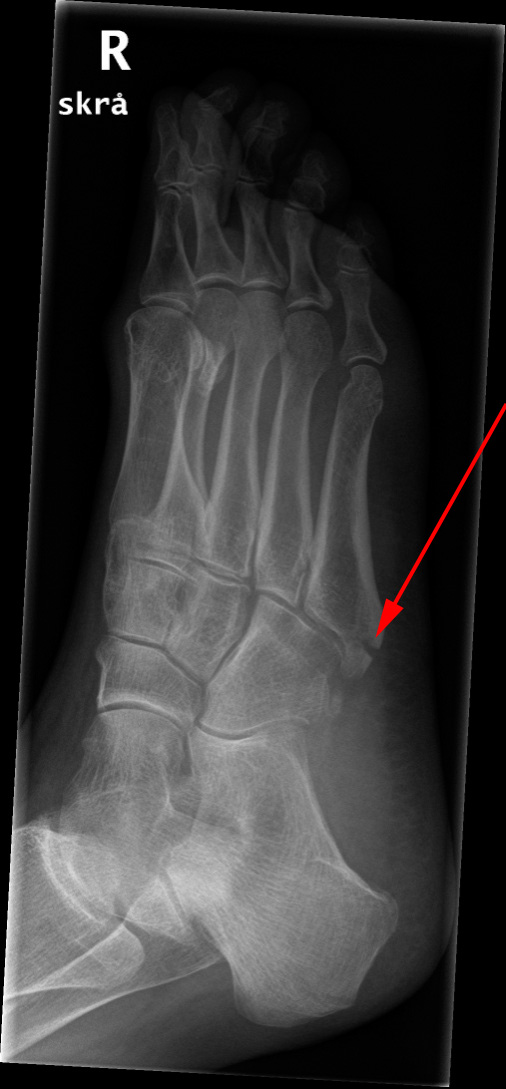

Metatarsfraktur, røntgen

Røntgenundersøgelse af foden viser en fraktur i 5. metatars (rød pil).